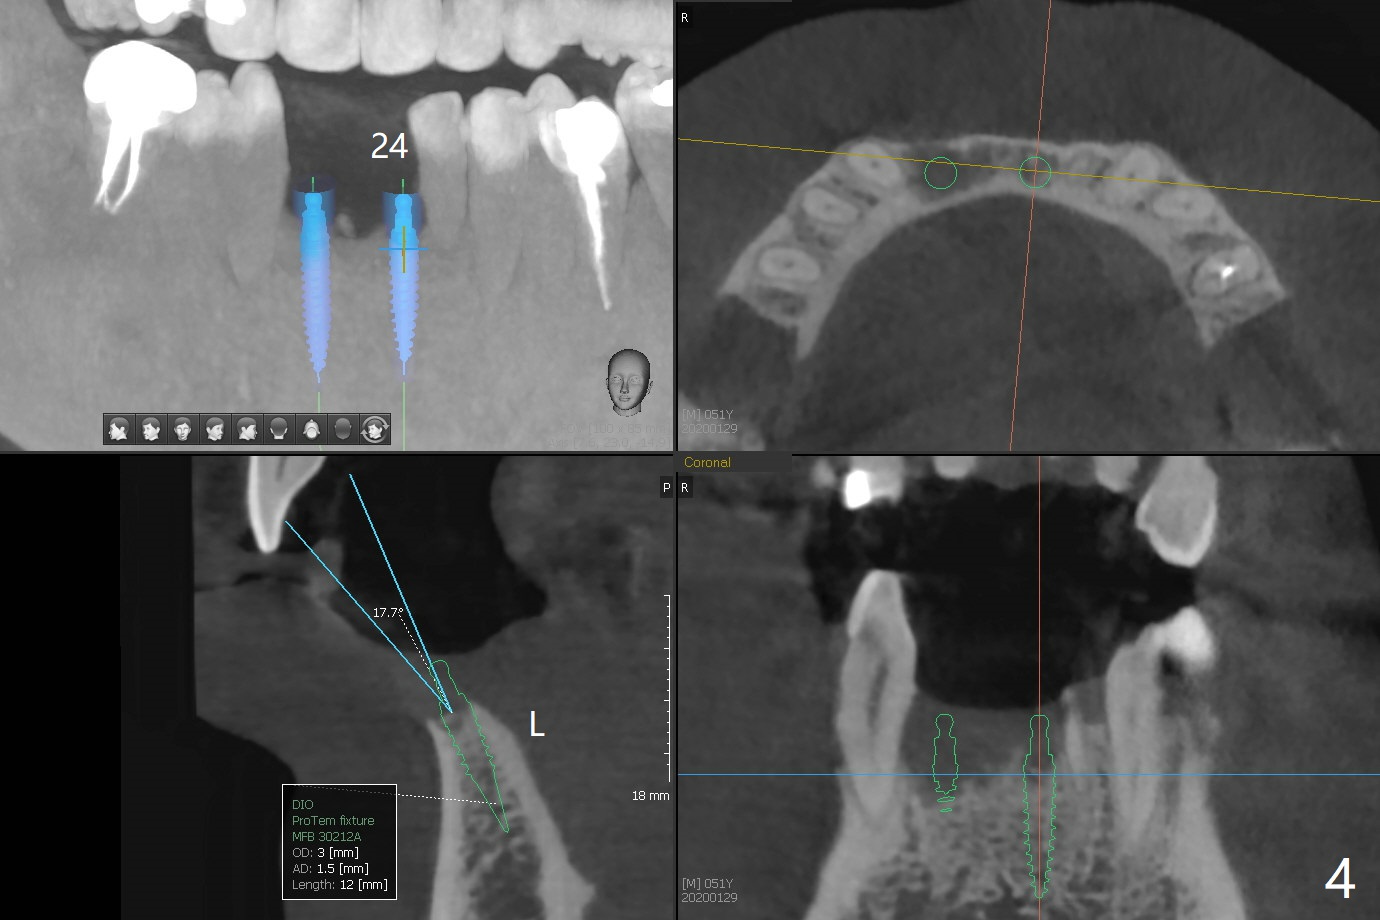

A 51-year-old man with chronic periodontitis requests implants at 19, 24-26 and 30 nearly 2 months post extraction without bone graft (Fig.1). He is willing to quit smoking by using electronic smoke. After SRP, the tooth #6 with supragingival fracture will be saved by post and crown. The mesiodistal space seems to be too narrow for implant (Fig.2). 1-piece implants will be placed at #24 and 26 for FPD (Fig.3,4). Implant placement at #19 and 30 will involve incision, socket redebridement, guide, bone graft (sticky bone), PRF membranes as a barrier and sutures (Fig.5,6).